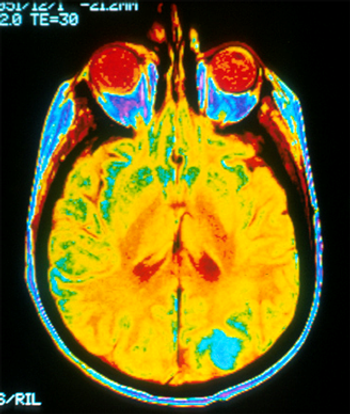

Neurological disorders have been considered a significant threat to public health for some time. Take a look at these facts and figures.